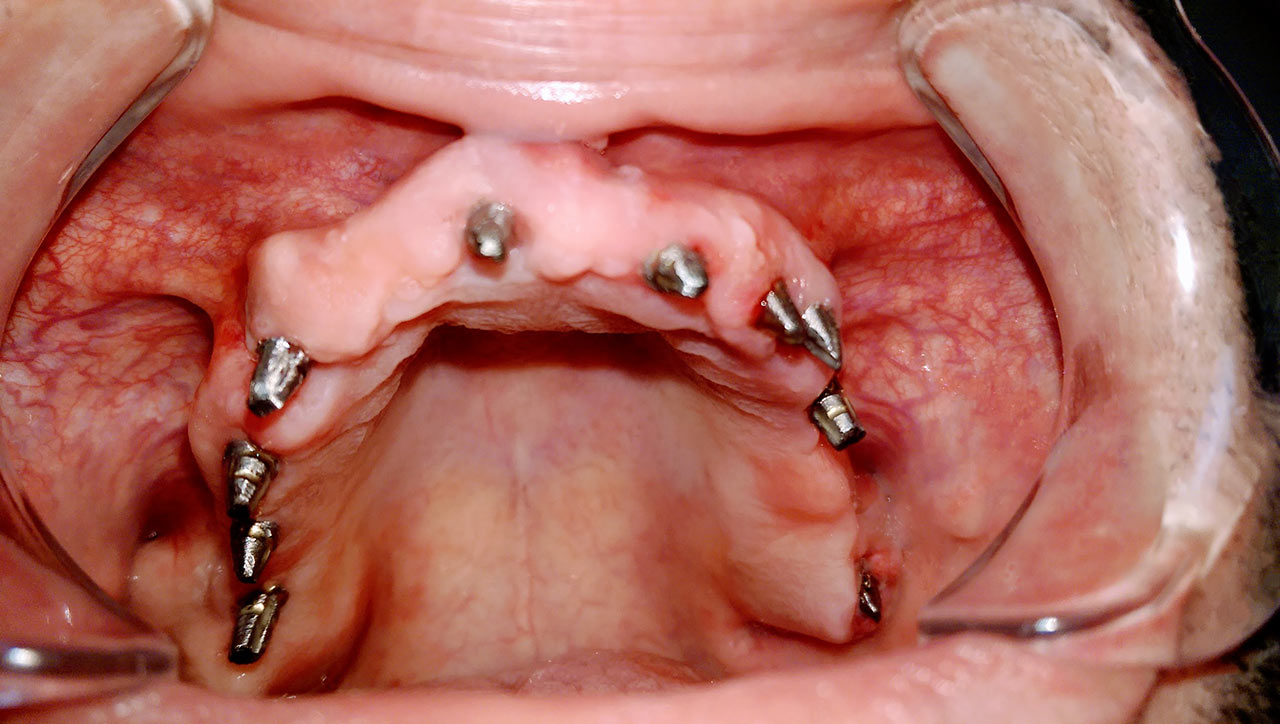

2 nap alatt varázsoltuk ezt a szép esztétikus alsó, felső körhídat implantátumokkal megtámasztva a korábban elhanyagolt szájba. Az 1. nap 26 fogat távolítottunk el, mert annyira rossz állapotban voltak, és rögtön azonnal terhelhető IHDE svájci implantátumokat raktunk be, fentre 8, lentre 6 darabot. A sebeket összevarrtuk és intraorális szkennerrel digitális lenyomatot vettünk. 2 nap múlva pedig beragasztottuk a kész PMMA műanyag körhidakat. Dr. Kelemen Péter és a Symbion Fogtechnika munkája.